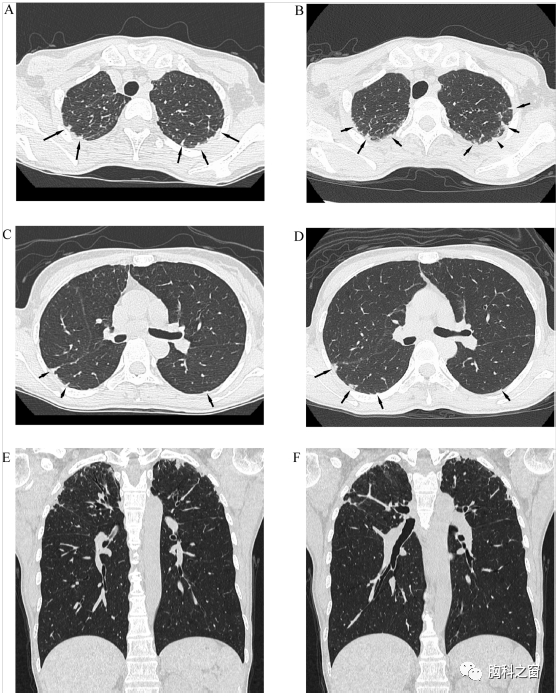

日常实践中ct上的胸膜肺实质弹力纤维增生症ppfe样表现患病率和系列

图片尺寸558x697